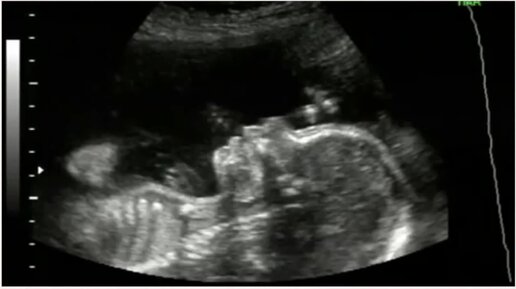

УЗИ на 22 неделе беременности

Медицинский женский центр